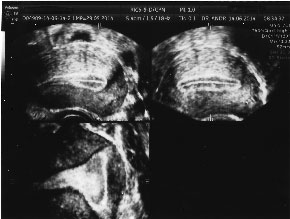

![]() | ![]() |

| Cavitate uterina discret arcuata. Arhiva personala Dr. Lara Andronescu | Cavitate uterina cu coarne alungite. Arhiva personala Dr. Lara Andronescu |